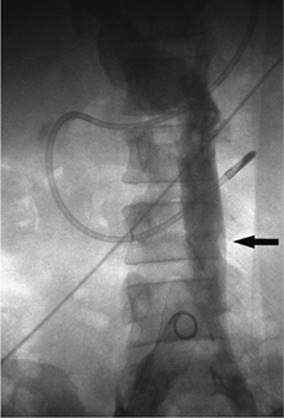

000459

Figure 35.24. Attempted canalization of the portal vein during a transjugular intrahepatic, portacaval shunting (TIPS) procedure. The tip of the cannula is in the left hepatic duct (black arrow). Contrast is noted throughout the biliary system and into the common bile duct (white arrow).

Puncturing the portal vein has proved to be difficult in some cases. Thrusting a large needle blindly through the liver parenchyma can cause a host of complications including bleeding from the liver capsule if the needle perforates the capsule of the liver. Hemobilia can be seen if the needle perforates a bile duct in close proximity to a vascular structure. The needle may leave the capsule of the liver and puncture adjacent organs including the intestine, gallbladder, kidney, and aorta, among others (Figs. 35.22–35.24).